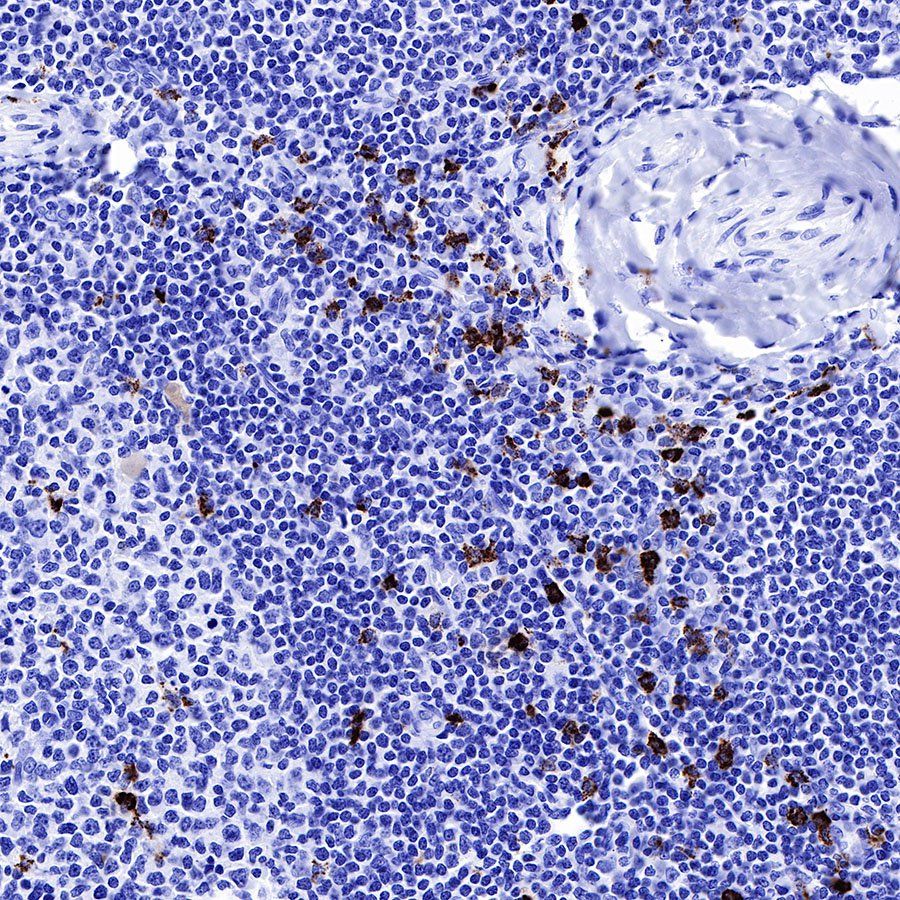

IHC shows positive staining in paraffin-embedded human tonsil. Anti-MPO antibody was used at 1/1000 dilution, followed by a HRP Polymer for Mouse & Rabbit IgG (ready to use). Counterstained with hematoxylin. Heat mediated antigen retrieval with Tris/EDTA buffer pH9.0 was performed before commencing with IHC staining protocol.

IHC shows positive staining in paraffin-embedded human spleen. Anti-MPO antibody was used at 1/1000 dilution, followed by a HRP Polymer for Mouse & Rabbit IgG (ready to use). Counterstained with hematoxylin. Heat mediated antigen retrieval with Tris/EDTA buffer pH9.0 was performed before commencing with IHC staining protocol.